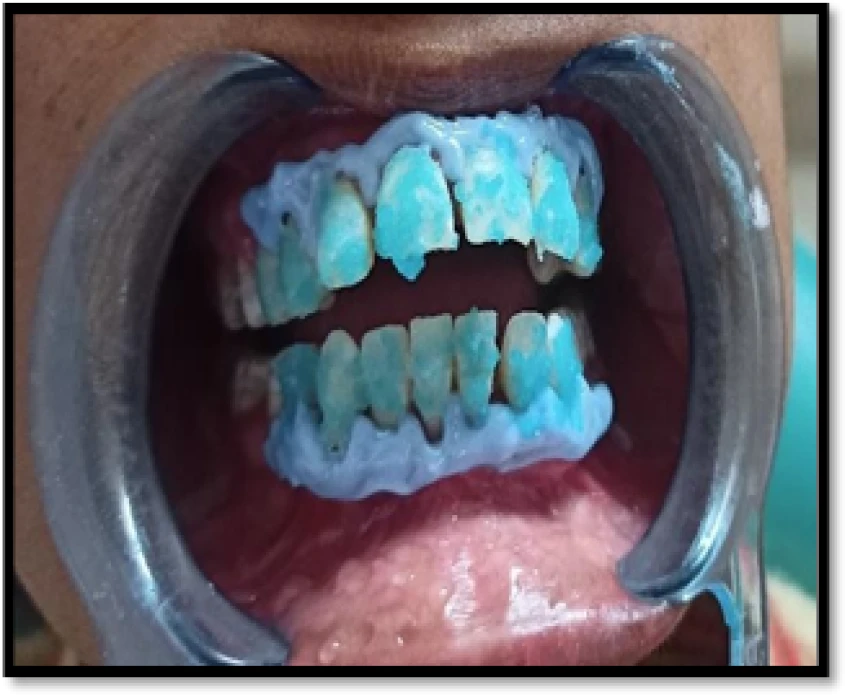

Liquid Dam (Gingival barrier) was applied and cured for gingival protection and isolation.

For this patient, Pola Office was chosen as bleaching agent. Equal part of bleaching gel and powder was taken and mixed until thick homogeneous mixture was formed and applied over teeth using applicator tip